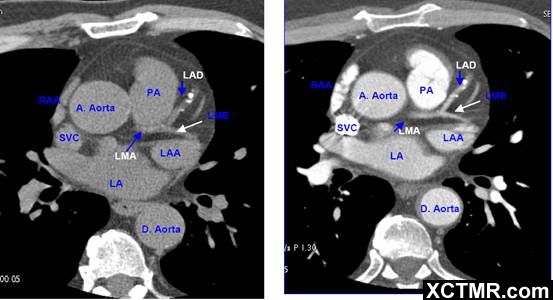

常用英文名称及缩写 LA - Left Atrium 左心房 RA - Right Atrium 右心房 LV - Left Ventricle 左心室 RV - Right Ventricle 右心室 Mitral Valve 二尖瓣 A. Aorta-Ascending Aorta 升主动脉 D. Aorta-Descending Aorta 降主动脉 SVC – Superior Vena Cava 上腔静脉 IVC – Inferior Vena Cava 下腔静脉 PA - Pulmonary Artery 肺动脉 PV - Pulmonary Vein 肺静脉 LMA - Left Main Artery 冠状动脉左主干 LAD - Left Anterior Descending Artery 左前降支 LCX - Left Circumflex Artery 左回旋支 LMB - Left Obtuse Marginal Branch 左边缘支(钝缘支) RCA - Right Coronary Artery 右冠状动脉 PDA - Posterior Descending Artery 后降支 Conus Branch 右动脉圆锥支 LAA – Left Atrial Appendage 左心耳 RAA – Right Atrial Appendage 右心耳 CS - Coronary Sinus 冠状窦 MCV – Middle Cardiac Vein 心中静脉 GCV –Great Cardiac Vein 心大静脉 PIVV – Posterior Intraventricular Vein 后室间静脉(心中静脉) PLVV – Posterior Left Ventricular Vein 左室后静脉 PLV – Posterior Lateral Vein 左室后侧静脉(边缘静脉) | |